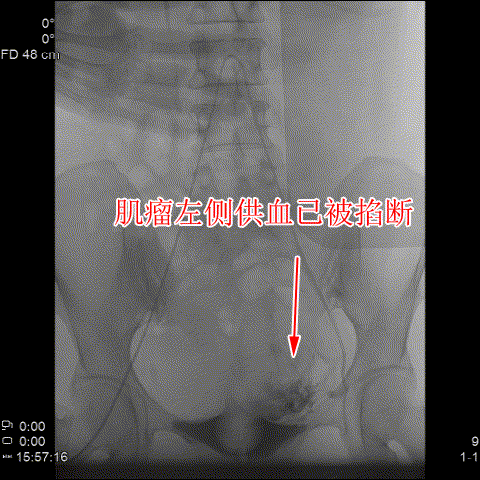

△術後造影可見肌瘤左右側的供血已被掐斷。

随後,李旭丹主任與胡志華主任聯手爲患者實施手術,通過患者股動脈穿刺,置入微導絲、導管,經動脈自然腔道将導管送達左右側髂總動脈進行造影,可見肌瘤供血血管,随後利用微導管将特制栓塞材料送達子宮動脈進行栓塞。造影顯示子宮肌瘤供血已被掐斷,順利完成手術。